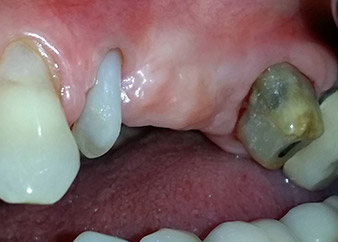

Mujer de 58 años de edad, que además es una apreciada colega y amiga, y se quejaba de dolor y de un aumento en la movilidad del pilar del puente de la pieza dental 24. También había inflamación periodontal, con bolsas de una profundidad de 7 mm en sentido mesiobucal y más de 12 mm en sentido distal, así como furcación de tercer grado. Asimismo, la radiografía reveló una lesión periodontal extensa alrededor de la región apical de la pieza dental 24 (figura 1) tratada previamente con endodoncia (alio loco).

Un año antes, las piezas dentales 25 y 26 se habían extraído por razones traumáticas y endo-periodontales antes de la colocación del puente. Se diagnosticó una lesión endo-periodontal combinada en la pieza dental 24, pero su componente etiológico principal no estaba claro. La paciente declaró su voluntad de mantener el pilar del puente de las piezas 24 y 27 y afirmó que no aceptaría una prótesis extraíble final, ni siquiera provisional. Por lo tanto, se acordó intentar por todos los medios conservar ambos dientes, a pesar del mal pronóstico que mostraban las pruebas radiológicas y clínicas.

Después de la medicación tópica con un 25 % de gel de metronidazol (Elyzol) en las bolsas de la pieza 24, se inició un tratamiento causal de terapia periodontal con desinfección de toda la boca. El tratamiento ortógrado del canal radicular se revisó mediante una obturación con gutapercha termoplástica, un poste de fibra de vidrio y una acumulación de núcleo de composite (figura 2). El puente se recementó fuera de la oclusión para permitir la cicatrización sin problemas de los lugares de la GTR y la GBR.